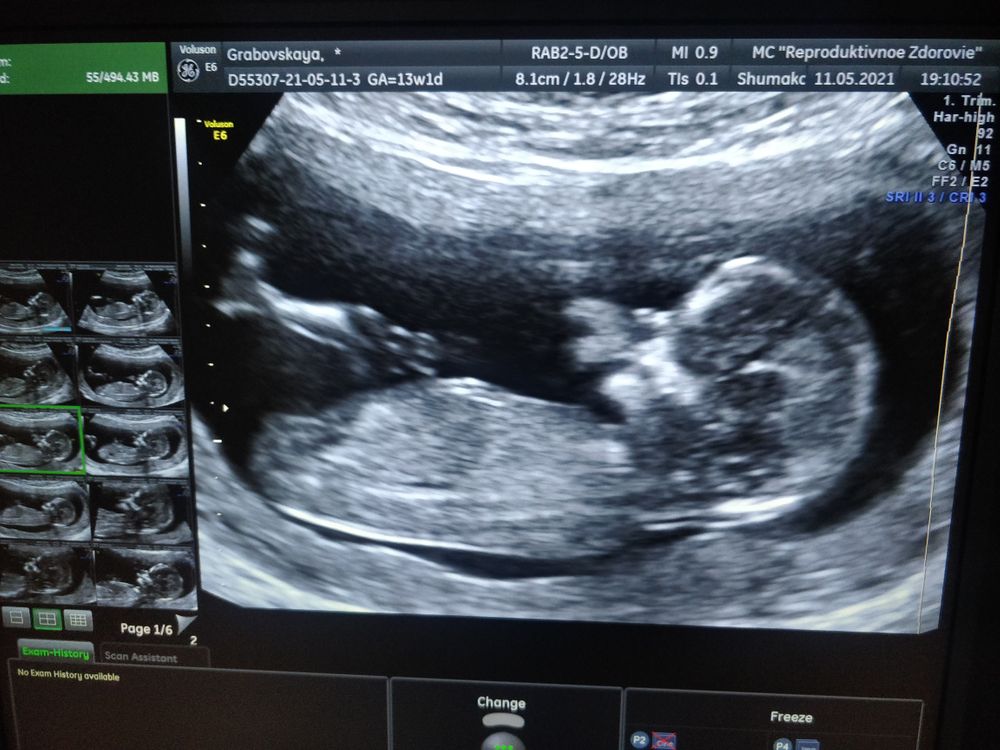

11 мая мы с мужем съездили на 1 скрининг!!! Какое же это счастье увидеть такое маленькое сокровище ❤️😍🤗. По сроку мы 13+1, на Узи ставят 13+5 💪.

Когда врач смотрел и делал замеры, он сразу увидел кто у нас живёт в домике. Спросил, хотим ли мы знать пол ребёночка, я конечно же сказала что очень хотим. И у нас ДЕВОЧКА 🎉💃❤️

У нас все хорошо, растем по норме, девчуля у нас длинноногая, вся в папу 😄.